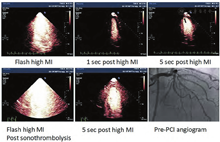

诊断性超声探头发出的间断性高机械指数脉冲超声溶解血管内血栓的潜能最初在犬动静脉移植血管血栓模型上得到验证。在这个实验中,低机械指数脉冲成像探测移植血管中微泡的同时给予间断高机械指数脉冲(均<1.9)[129]。高机械指数脉冲诱发了血管内的瞬时空化现象,从而形成了流体喷射,实现了机械溶解血栓[130]。高机械指数脉冲在没有任何促纤维蛋白溶解、抗血栓或抗血小板药物辅助的情况下实现了血管再通,这表明体外实验观察到的高机械指数脉冲的空化和辐照效应具有溶解血栓的能力。这项研究促进了后续关于高机械指数脉冲对猪急性ST段抬高心肌梗死模型的微血管和心外膜下大血管血流恢复功效的探索研究[131,132]。由于在诊断超声(DUS)检查时心外膜大血管不易观察,于是这些研究使用了VLMI微循环成像来指导高机械指数脉冲的使用时机。即使存在胸壁组织的衰减,这些研究同样证明了从诊断超声探头发出的间断性高机械指数脉冲可以增加心外膜冠脉再通率,从36%(单独使用半剂量的组织纤溶酶原激活物)到83%(同时使用诊断超声高机械指数脉冲结合微泡及半剂量组织纤溶酶原激活物)。此外,使用诊断超声高机械指数脉冲时,即使在未见心外膜冠脉再通的情况下,也可见ST段回落(表明微血管再通),这提示血管活性调节介质在恢复微循环血流及在心外膜冠脉血栓溶解中也发挥作用。随后的缺血性外周血管闭塞的研究也证实,即使存在上游血管闭塞的情况下,高机械指数脉冲能诱导一氧化氮的释放,从而促进微循环血流的恢复[133]。急性ST抬高心肌梗死患者的初步临床研究表明,超声引导的诊断性高机械指数脉冲(3 μs脉冲持续时间)以及通过静脉注射市售微泡足以提高早期心外膜大血管再通率及恢复微循环血流 (图18)[134]。目前正在进行的研究将检测诊断超声靶向超声溶栓技术在急性冠脉综合征和缺血性脑卒中应用中的安全性及有效性。

MCE已被应用于评估ST段抬高型心肌梗死(STEMI)急症处理后静息微血管血流量[56,121]。即使在梗阻血管早期成功再通后,梗死区域内静息微血管的持续灌注缺损对于不良左心室重构和再发心脏事件(死亡和再次梗死)有独立的预测价值。尽管数据有限,VLMI下UAE似乎可以同时获得STEMI患者出院前两项重要预后指标的评估,即左心室收缩功能和微血管阻塞程度。

尽管现代的经皮介入技术可以实现血管造影证实的再通和正常的心外膜血流,但微血管阻塞仍可能存在于相当大比例的患者中,并对预后也相当重要(图17)。